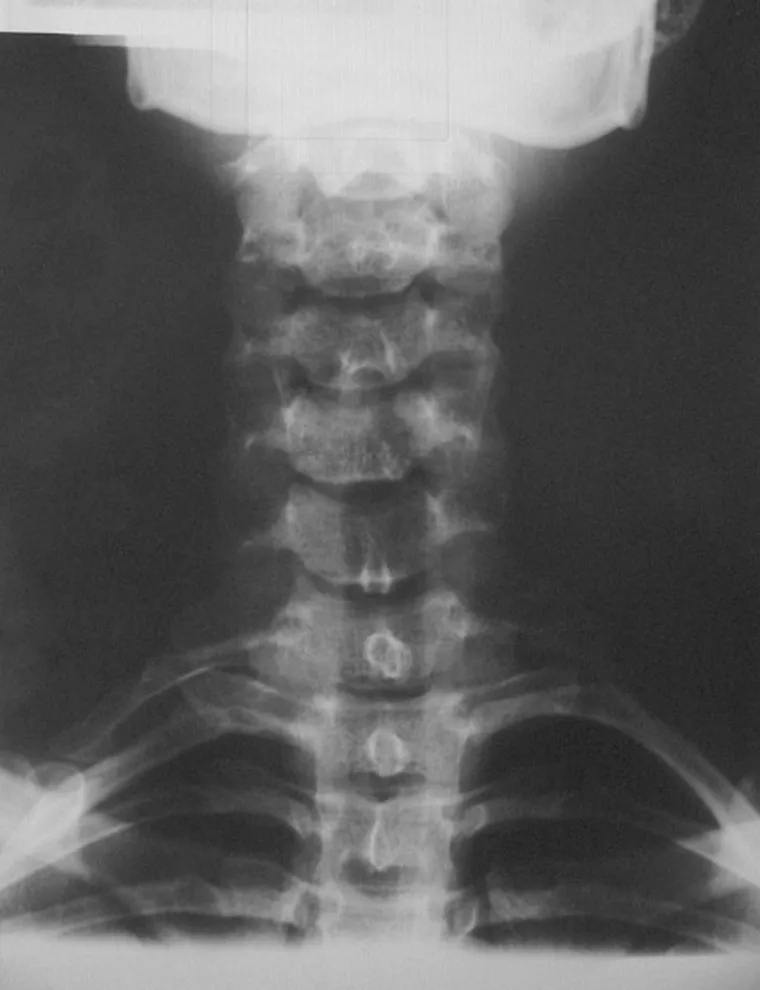

Nyaki borda Nyaki borda Kétoldali nyaki borda a hetes, egyoldali a hatos nyakcsigolyán. Kategória Diagnosztika Közzétéve: 2016. 04. 23. 14:49